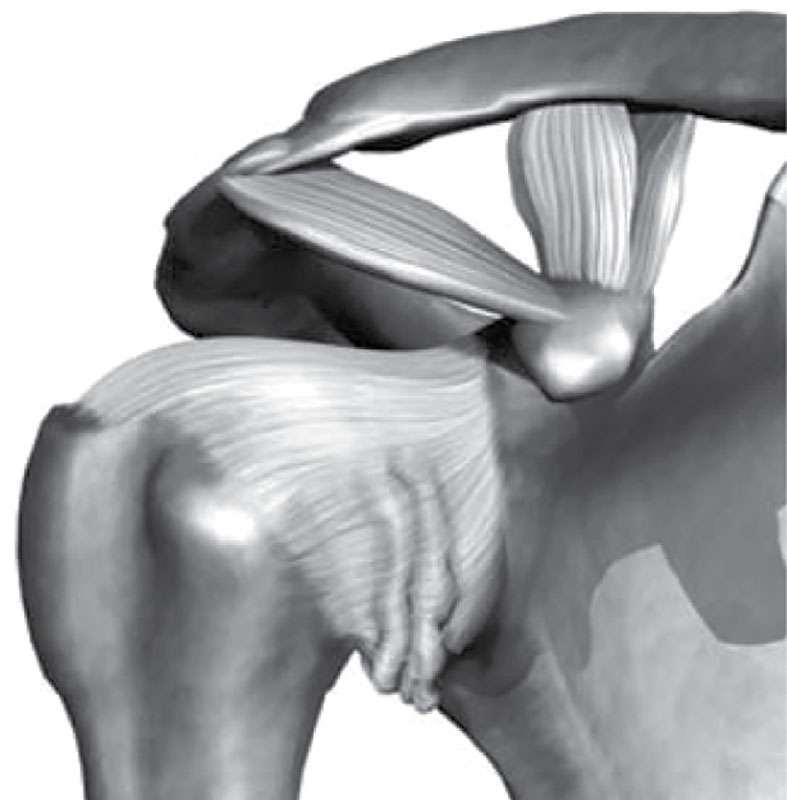

Фотографии поддельтовидной мышцы плечевого сустава